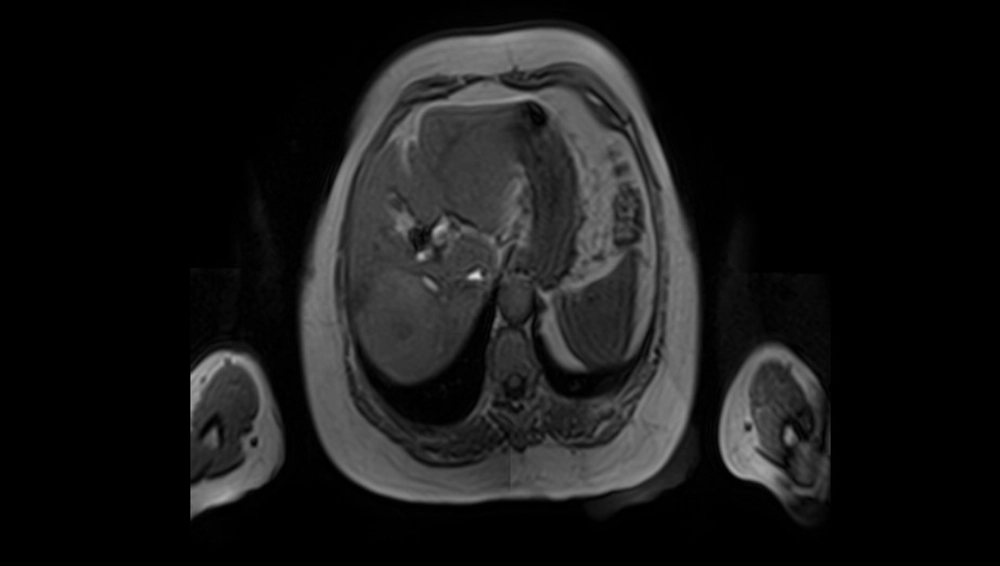

Systemic chemotherapy was started with the aim of reducing the size of the lesion and facilitating surgery with a greater possibility of negative margins and an adequate liver remnant, receiving 7 cycles of atezolizumab + bevacizumab. (Figure 1)

Figure 1. Magnetic resonance axial section T1 with 6cm lesion in right hemi liver.